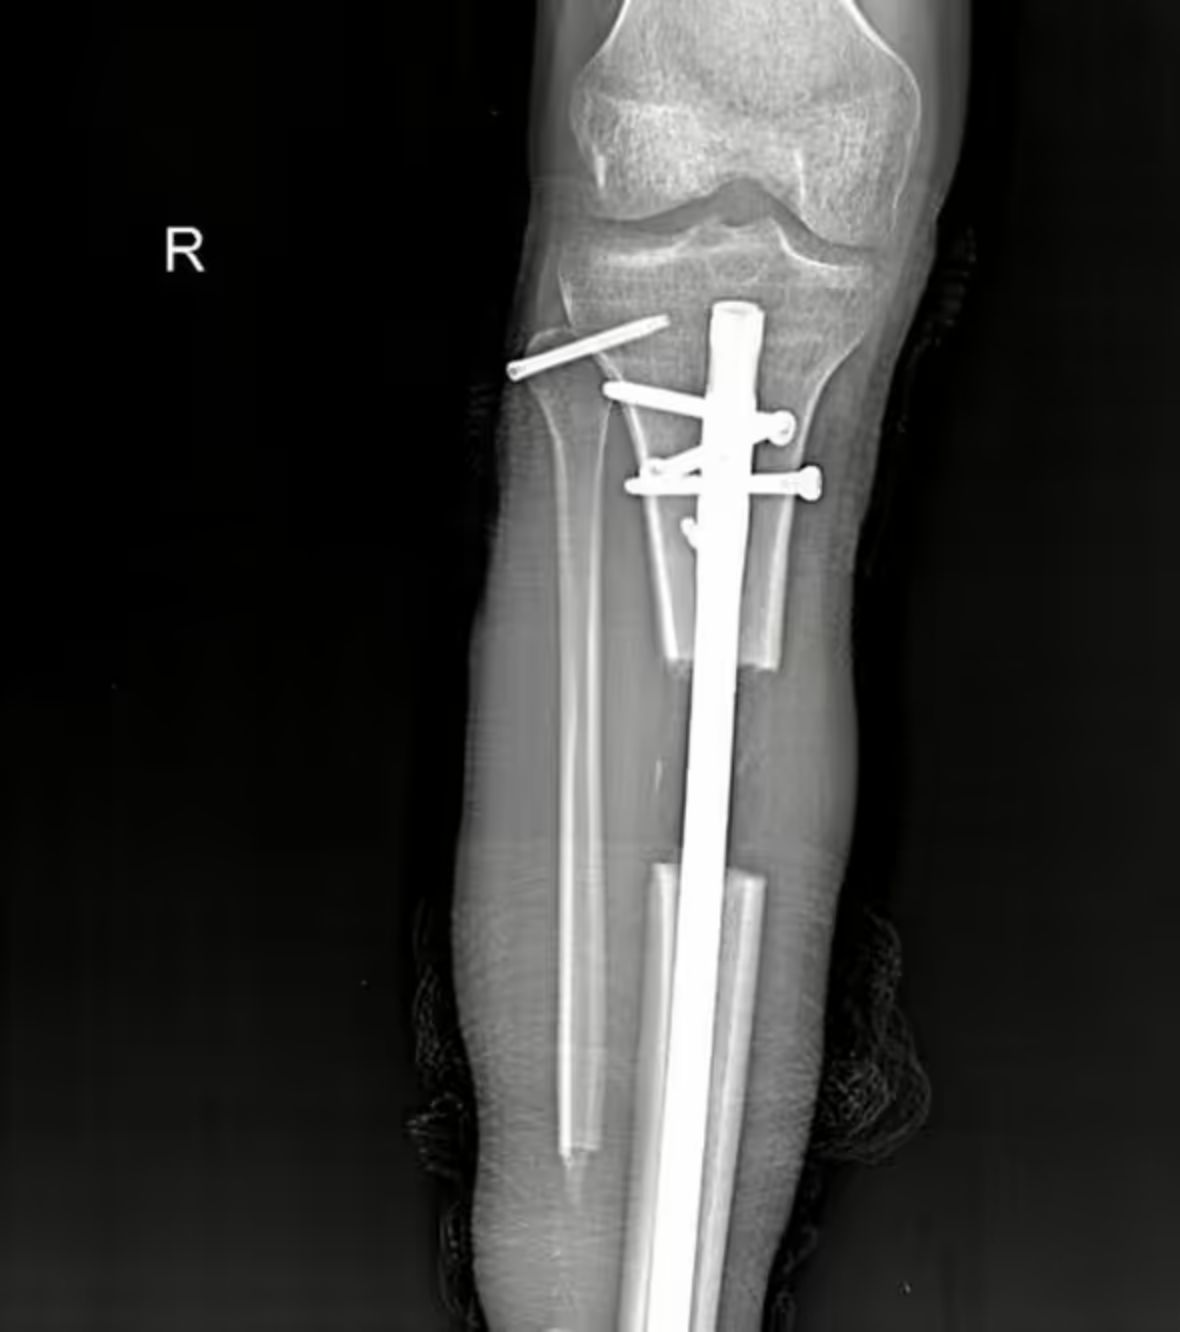

Operasi pemanjangan kaki yang dilakukan Dynzell disebut sebagai 'lengthening over nail' atau LON. Prosedur ini dilakukan dengan cara mematahkan kedua tulang kaki, kemudian dokter akan memasang semacam gagang dengan paku di antara patahan tersebut.

Kemudian gagang yang tertanam dalam kaki akan dipanjangkan secara perlahan setiap enam jam sekali. Seiring berjalannya waktu, dengan rehabilitasi dan fisioterapi rutin, tulang akan menjadi lebih kuat sampai akhirnya bisa menopang tubuh tanpa bantuan.